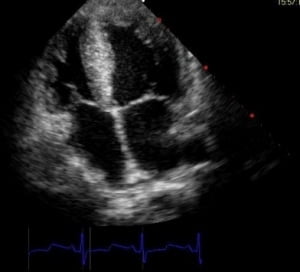

La ecocardiografía Transtorácica

Comparando con la ETE, la ETT no es invasiva y depende más del método usado y del profesional. Se coloca la sonda de ecografía en el tórax del paciente a nivel del esternón para poder visualizar las 4 cámaras cardiacas.

Para poder determinar con seguridad la posición de la punta del catéter central mediante ecocardiografía se requiere un alto nivel de conocimiento en imágenes ecográficas y su curva de aprendizaje es larga.

No existe una estandarización de las técnicas, sin embargo, hoy por hoy la ecocardiografía es el método más preciso para localizar la punta de una vía central, superando la precisión de la fluoroscopia.

Ambos tipos de ecocardiografía son técnicas seguras. La ETE es la más precisa de las dos.